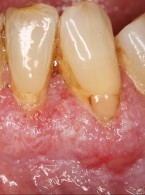

Pemfigoid błon śluzowych – trudności diagnostyczno‑lecznicze (...)

Zobacz więcej

12.50PLN